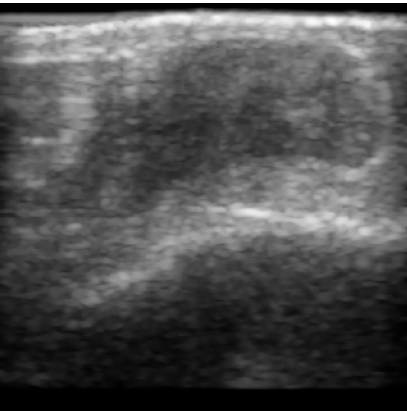

Figure 2: (a-d) Four representative US wound images. (e-h) Visualization of corresponding segmentation predictions for FCN. Green indicates correct matches, red and yellow indicate missed (false negative) and oversegmented (false positive) areas, respectively.

Table 2 shows the quantitative evaluation of the algorithms. U-Net and FCN both achieve a Dice score of 0.340.340.34 compared to pre-trained ResNet-U-Net which has a Dice score of 0.270.270.27. Visualizations of the segmentation results for FCN are shown in Figure 2, where (a-d) are the original inputs, and (e-h) the corresponding color-coded outcomes. In general, the performance is promising for a number of cases, although we see a high FP rate (d,h) for others. Table 3 shows the ratio of m¯rsubscript¯𝑚𝑟\overline{m}_{r} for different wound regions compared to m¯wsubscript¯𝑚𝑤\overline{m}_{w} of the whole wound area. In the wound center, the US values are lower (ratio: 0.89 ±plus-or-minus\pm 0.11), compared to the wound borders (ratio: 1.47 ±plus-or-minus\pm 0.37).

In this work, we showed a proof-of-concept for a non-invasive imaging technique paired with machine learning. We performed initial experiments for automatic segmentation of US wound images with deep learning which show an Dice score of 0.340.340.34 for both U-Net and FCN and 0.270.270.27 for ResNet-U-Net. The segmentation results strongly depend on the quality of the scan and the specific wound type. Quantitative results can still be improved but the visual examination of the results indicates applicability of the proposed setup. For images illustrated in Figure 2(e-g), the segmentation is very good. However, the network misclassifies the region beneath the hyperechoic bone surface (image h) as this region therefore appears dark and similar in intensity to the wound region.